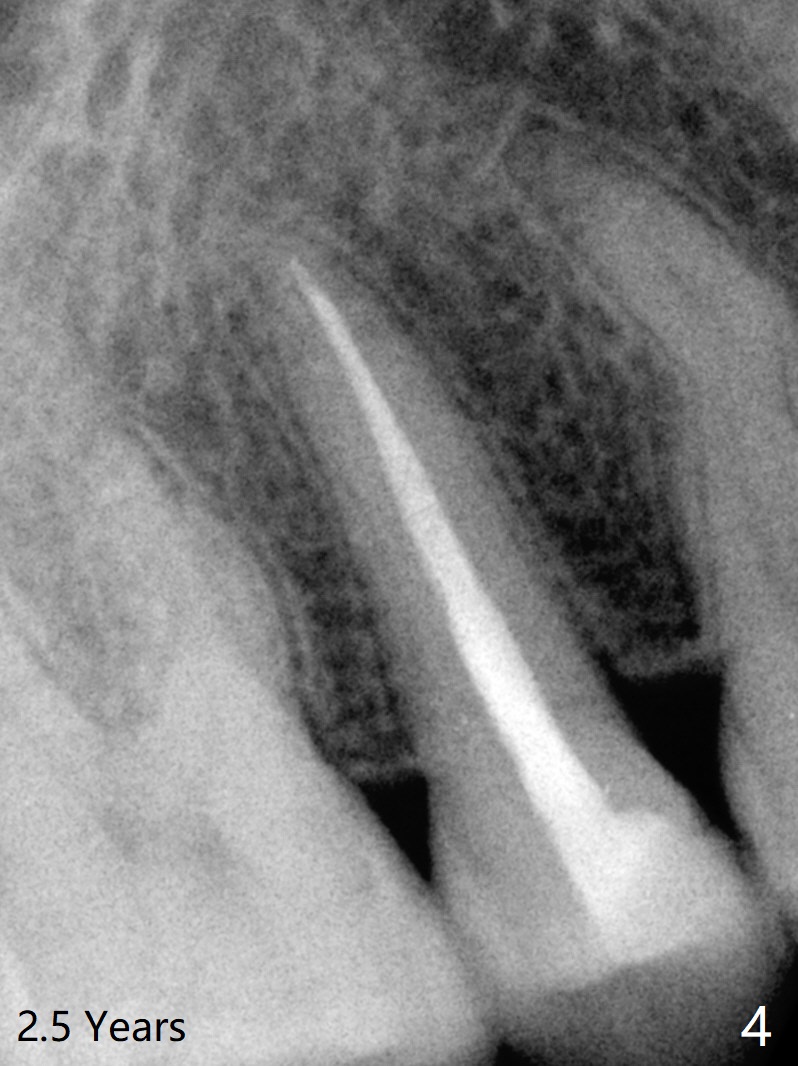

A 29-year-old woman presented to office with multiple amalgam restoration 7 years ago. The tooth #4 developed acute pulpitis 7 months later (Fig.2). The tooth has 2 fused canals; after RCT, composite was placed; after discussion, the patient chose no crown (Fig.3). There is no recurrent periapical radiolucency or tooth fracture 2.5 (Fig.4) or 6.5 (Fig.5,6) years postop.